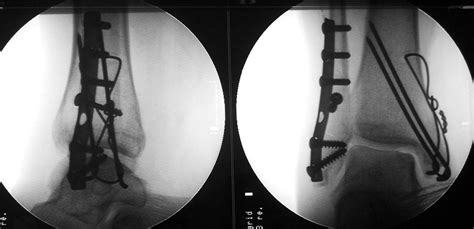

Displaced trimalleolar fracture of unspecified lower leg. Plain radiographic interpretation in trimalleolar ankle fractures poorly assesses posterior fragment size. The trauma is sometimes accompanied by ligament damage and dislocation.

Common codes clinical documentation tips clinical scenarios. Figure 28a figure 28b figure 28c findings supine anteroposterior (ap) radiograph of the ankle (fig. To code a diagnosis of this type, you must use one of the nine child codes of s82 that describes the diagnosis 'fracture of lower leg, including ankle' in more detail. Fracture fixation, internal / instrumentation. The fractures involve the medial malleolus, the posterior aspect of the tibial plafond (referred to as the posterior malleolus) and the lateral malleolus. Ankle fractures can be classified based on the number of malleoli involved, namely unimalleolar, bimalleolar or trimalleolar fractures 6. The fracture description above is well defined and includes description that supports the necessary items such as traumatic, open, displaced, middle of femur shaft, subsequent encounter, routine. Displaced trimalleolar fracture of unspecified lower leg. Trimalleolar fractures are similar injuries. The area that is affected is the medial malleolus, posterior malleolus and the lateral malleolus. These are unstable injuries and they can be associated with a dislocation. The patient slipped on wet steps during a rain storm. The reduction and splinting of a trimalleolar fracture and ankle dislocation is shown in this video. Compensation for trimalleolar ankle fractures. A fractured ankle can range from a simple break in one bone, which may not stop you from walking, to several fractures, which forces your ankle out trimalleolar fractures means that all three malleoli of the ankle are broken. Trimalleolar fracture is a specific injury in the ankle, where three areas known as the malleoli break simultaneously. The medial malleolus of the tibia, as well as the lateral malleolus and posterior malleolus (in the lower portion of the fibula).